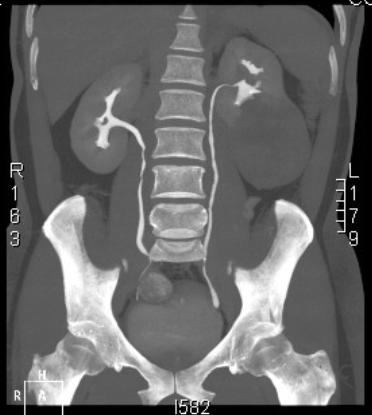

2014年9月10 日一如平常的生活節奏,萬萬沒有預料的事情居然會在不久之後對我當頭棒喝! 然而現在要認真追究這件事的因,為何得到如此的果? 依然沒有人可以拍板定案, 腦海中清晰地記得, 健檢時超音波掃描的醫師口吻平和的告訴我: 先生, 平常腰有沒有不舒服? 超音波掃描看到左邊的腎有一顆”巨大”的腫瘤, 趕快進行後續治療, 越快越好! 接近中午時分, 健檢中心的服務小姐親切地先把超音波掃描的結果給我, 並問我需不需要預約門診? 但是腦袋一片空白, 只是表面上答應著, 下意識想加強對身體的感知, 試著去感覺醫師告訴我的結果, 依舊是感覺良好, 沒 “FU”. 我想一般人面對這種事, 當下心裡的衝擊必然是大於生理, 但是做出的反應不一而足; 有的人會鑽牛角尖, 不停地問: 為什麼是我? 有的人知道之後六神無主, 求神拜佛, 任何機會都去嚐試; 有的人猶如被宣判死刑似的放棄希望… 那我的心理反應又是如何呢? 可能工作性格使然, 好比工程師遇到一個非常棘手的問題, 要如何拆除潛在問題的引信, 避免不預期的引爆, 造成無法收拾的後果. 首先這是一個不爭的事實, 老天沒有對你開玩笑, 我必須直面問題, 再來就是: 好了! 既然這是問題, 要怎麼處理才能達到目的或降低傷害到最小? 當然在處理的過程中, 心情的跌宕起伏或者內心的波濤洶湧難免, 此時的從”心”改變, 會反射出本人對問題抱持的正或負面態度, 都會影響到每一個判斷與結果, 也同時冥冥注定是否有貴人適時伸出援手, 助你度過生命中的低潮時刻! 經過這次無常的考驗, 我覺得最重要是當事人的心靈狀態, 它對結果起到決定性的影響, 因為一般人突然面臨生死關頭, 是毫無準備的而且沒有NG重來的機會; 可想而知心情是多麼恐懼、無助、紛亂! 就好像我在手術準備前, 雖然有家人的支持以及醫師充分的解說, 免不了還是會懷疑結束後是回到現實中抑或到了另外的世界? 為何我如此說呢? 因為無常在我恢復意識不久又演示一個活生生的例子在我眼前: 我在手術後恢復室待了約5小時, 妻子在外焦急地等待, 約凌晨2:45才被通知我已從麻醉中甦醒, 之後直到凌晨5:00送回病房前, 就處於意識清醒但身體無法自主, 傷口疼痛的感覺逐漸加強的狀態, 突然聽到工作人員叫道: 麻醉後血壓50, 30, 趕快與家屬聯絡…, 生死一瞬的戲碼就在我前面掠過. 所以生死大事是每人必修的功課, 如何在那一刻來臨時, 人生沒有遺憾或措手不及, 就必需在平時做功課, 讓自己的心時常處於”定”中, 不去追逐外界的五光十色, 不為慾望所牽絆, 如此才能由定中生起智慧, 鎮定地面對如此大事! 這次的經驗幸虧得到許多貴人的幫助, 才能如此順利! 整件事妻子忙前忙後, 在病榻旁細心照顧; 來自姊姊、小鳳以及上師與師父的心靈支持與關懷; 母親探病時輕撫我的手所流露的不捨和疼惜; 鍾醫師團隊的精湛醫術以及病房護理師們的專業照護…凡此種種, 都是我生命中的貴人. 除了感恩與感謝以外, 希望自己能夠做ㄧ個更好的人, 利益他人, 成為別人生命中的貴人. 提醒大家健檢有一定的重要性, 不要讓無常悄悄地找上而不知道! 祝身體健康 |